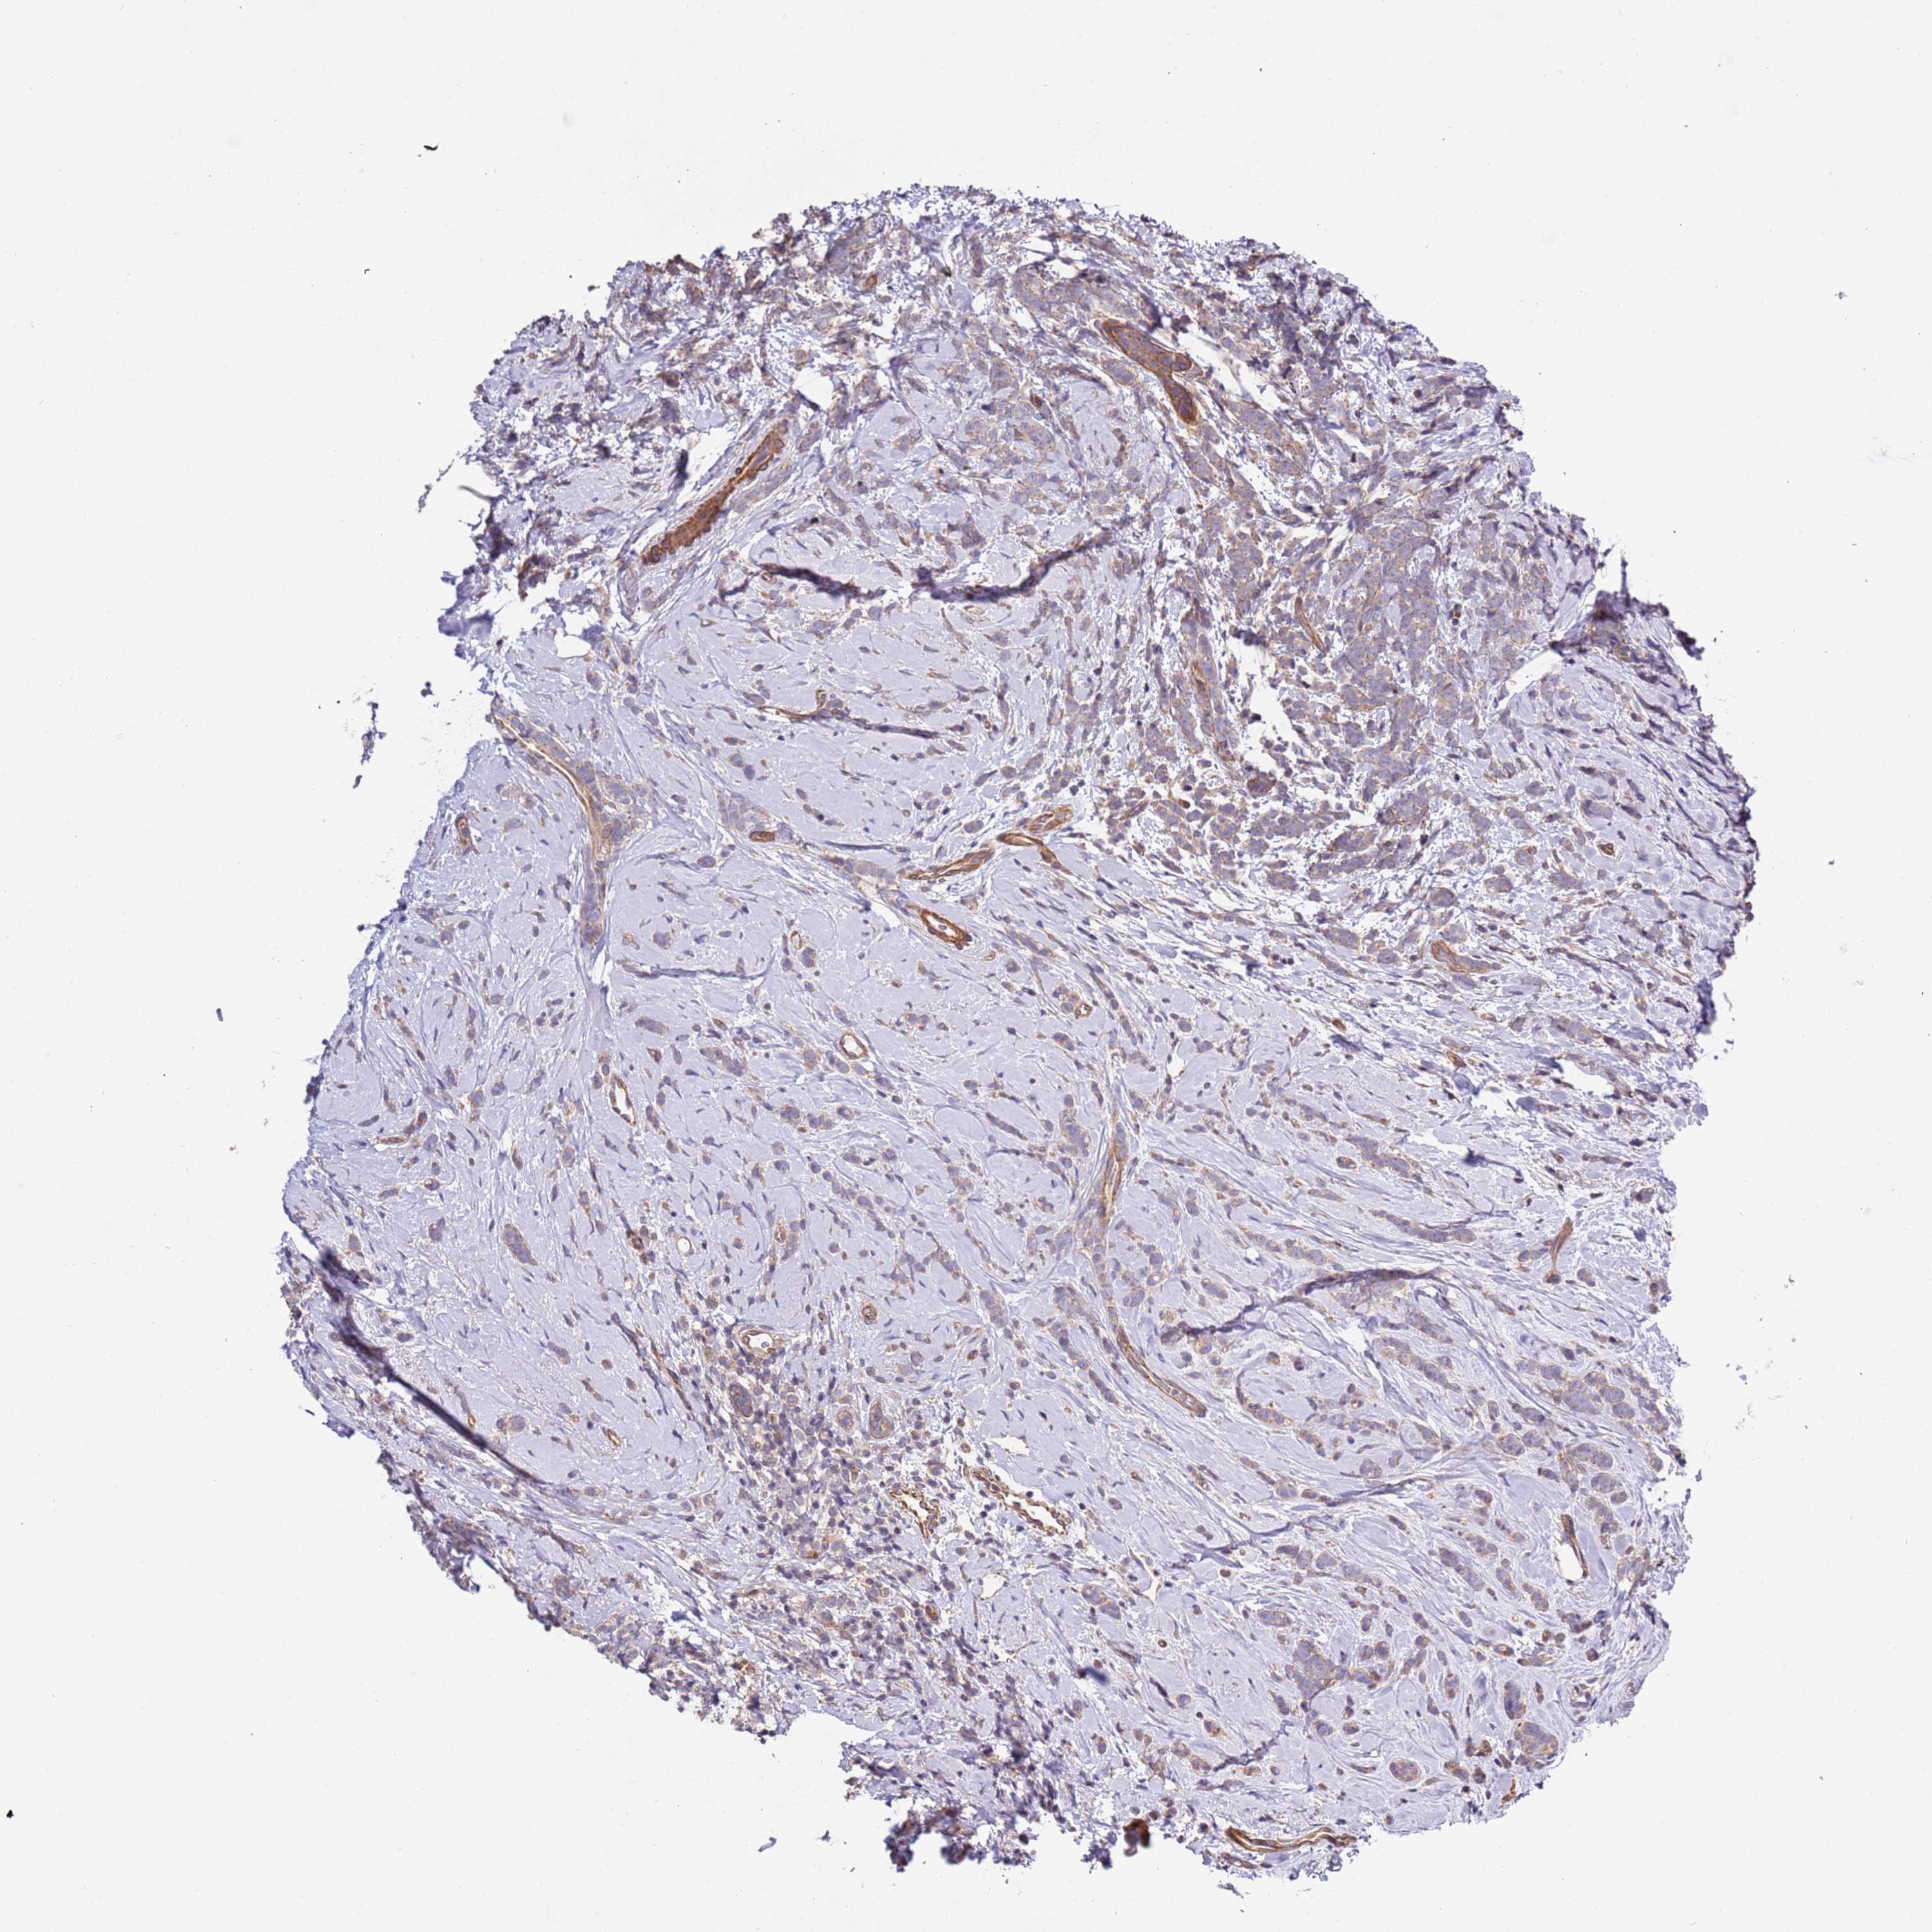

CANCER BREAST CANCER Show tissue menu

Breast cancer

Human cancer